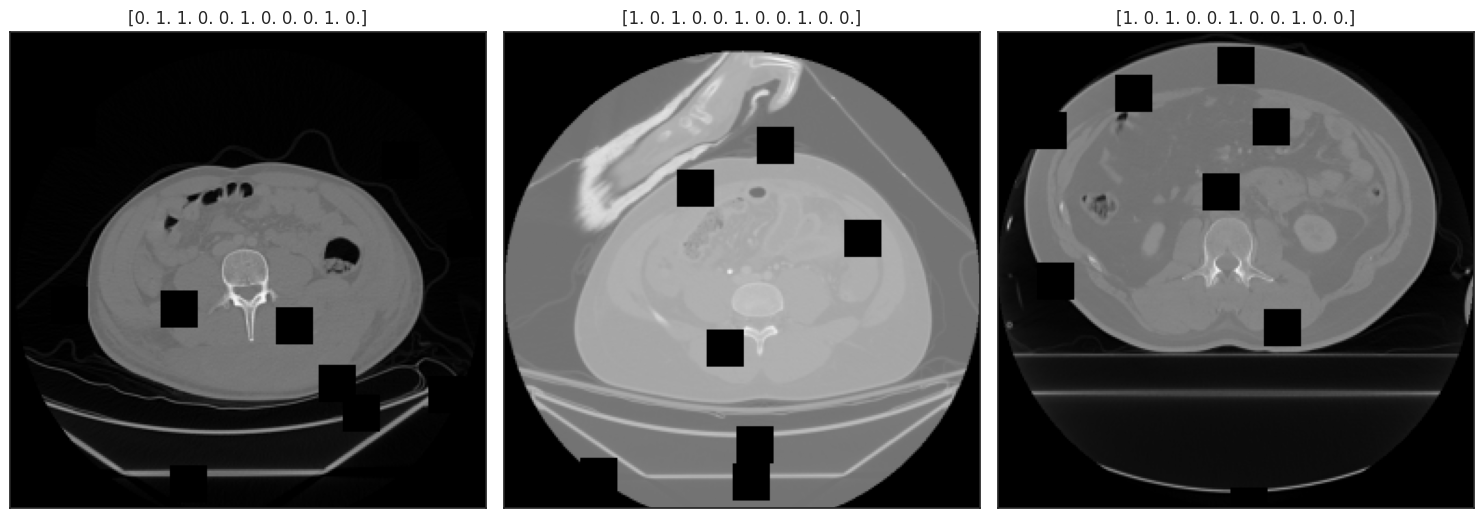

RNSA 2023 Abdominal Trauma Detection